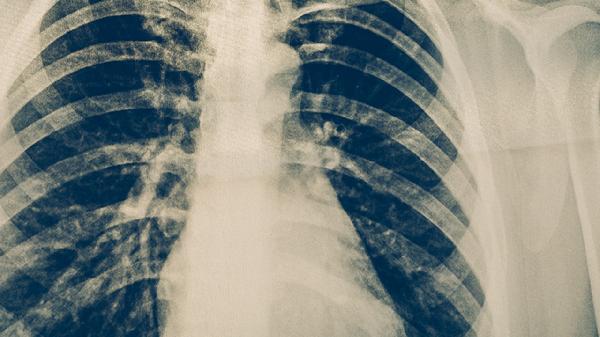

治疗期间需定期进行胸部影像学检查和痰结核菌检查,评估治疗效果。初期每月复查1次,病情稳定后可每2-3个月复查1次。复查内容包括胸部X线或CT、痰涂片、痰培养等。根据复查结果调整治疗方案,直至完成全程治疗。即使症状消失也不可擅自停药。